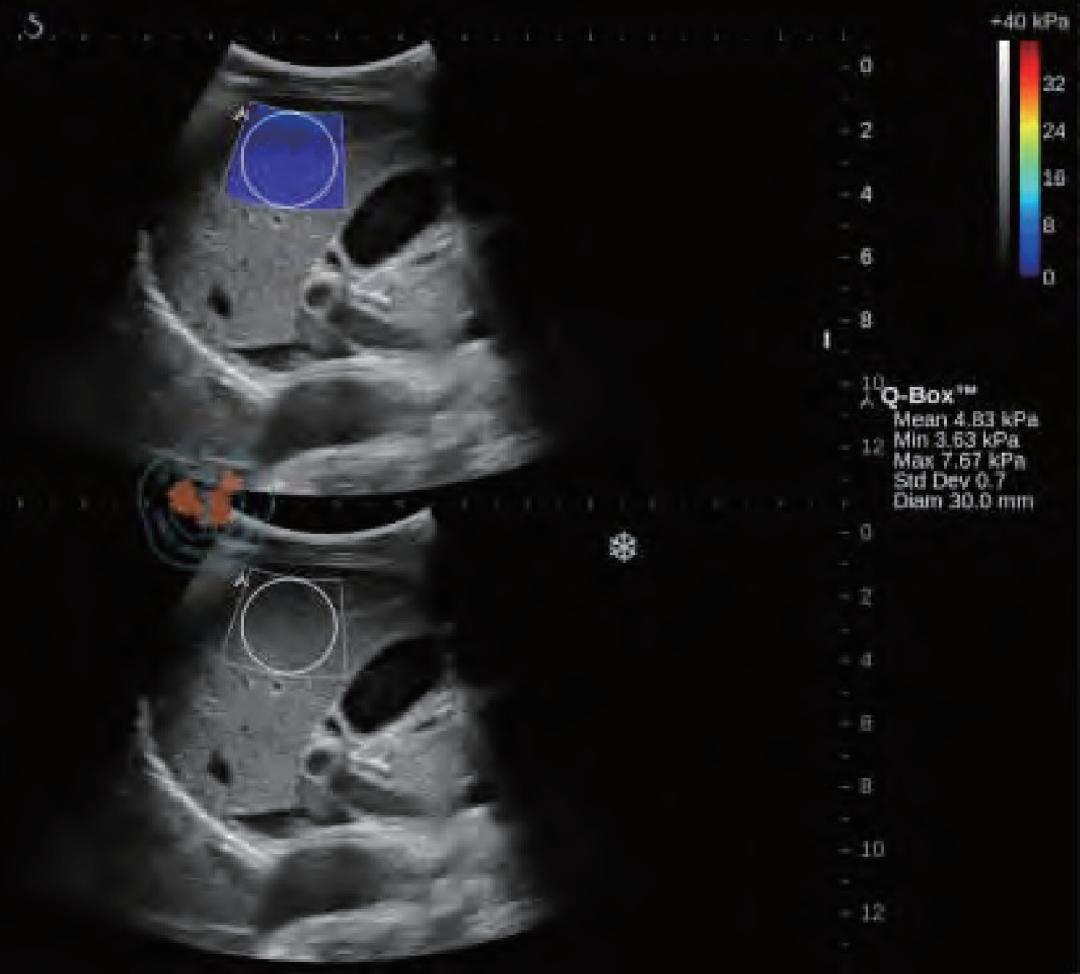

图12 慢性肝病患者的肝脏剪切波弹性成像及定量分析图。下图是原始的成像图,上图的蓝色区域则是在成像区域内选取直径为3 mm的圆形定量检测区域进行弹性模量的检测

谐波运动成像最早由Maleke等人提出。 通过探头产生的超声波对组织施加周期性的声辐射力,使组织产生谐波运动。 通过获取组织被激发前后的B超图像并对其进行运动估计,可以间接反映组织的弹性状况。该方法可以准确反映深部组织的局部弹性状况,但由于需要在激发信号的同时监测组织的运动,因而采集到的B超信号容易受到激发信号的严重干扰,这是该成像方法迄今为止尚未得到完美解决的主要问题。当声辐射力作用在组织上时会激发出剪切波,剪切波弹性成像正是通过检测这一剪切波的传播来达到成像的目的,最早由美国学者Sarvazyan和Emelianov提出。他们利用高强度聚焦超声探头产生声辐射力,在人体组织中产生了明显的剪切波,并运用磁共振成像方法监测该剪切波的传播情况。由于剪切波速与人体组织的粘弹特性紧密相关,因此通过检测剪切波的传播速度等参数可以获取组织的弹性信息。图12显示了某一慢性肝病患者的肝脏弹性成像图。声辐射力脉冲成像技术最早由杜克大学的学者Nightingale等人提出,该方法通过高能聚焦超声探头在局部组织中产生短暂的高强度声辐射力,从而推动组织产生一定的应变,再通过追踪这些微小应变和剪切波的传播来判断组织的粘弹特性。研究人员发现,组织对于脉冲声辐射力的瞬态响应直接相关于局部区域的硬度大小,而通过求解亥姆霍兹方程的反问题方法可以量化组织中剪切波的波速。Nightingale等通过详细的数值仿真和体模研究证实了声辐射力脉冲成像的可行性,并得到了与传统B超图像相比更高的对比度和分辨力。如今的声辐射力脉冲成像已在临床上具备多种脏器检查的能力,图13显示了某位良性纤维瘤患者的乳腺声辐射力脉冲成像图。